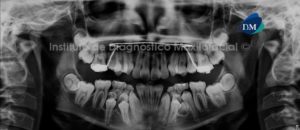

Paciente masculino, 13 años de edad es referido al Instituto de Diagnóstico Maxilofacial (IDM) para evaluación general y por leve molestias en el sector ántero